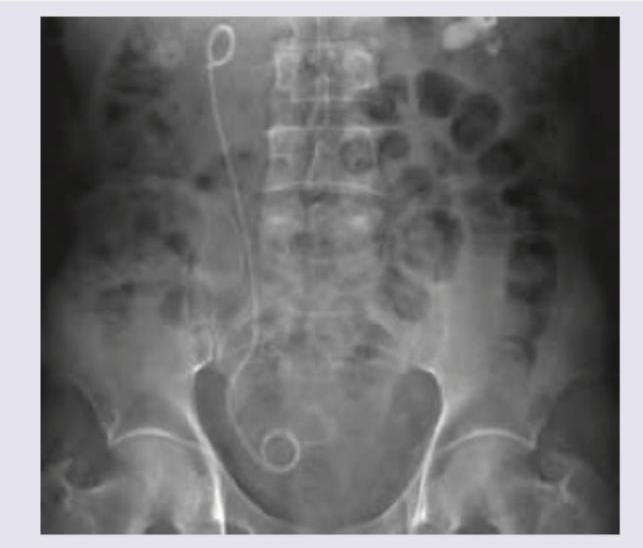

The radiographic image shows a stent in the urinary tract. This type of stenting is most commonly performed following which procedure?

Explanation: ***Stenting for pyeloplasty*** - The image shows a **double J stent** placed in the ureter, which is commonly used to ensure **urine drainage** and **prevent stricture** after reconstructive surgeries like pyeloplasty. - The stent extends from the renal pelvis (upper coiled end) down into the bladder (lower coiled end), typical positioning for urinary tract procedures. *Stenting for bile duct obstruction* - Stents for **bile duct obstruction** are placed within the biliary system, which is anatomically distinct from the urinary tract shown. - These stents would be visible in the upper abdomen, associated with the liver and pancreas, not spanning the kidney and bladder as seen here. *Stenting for ESWL* - **Extracorporeal Shock Wave Lithotripsy (ESWL)** is a procedure to break up kidney stones; stents may be placed before or after to facilitate stone fragment passage or relieve obstruction. - While a stent might be placed after ESWL, the image itself shows the placement and course of the stent, which is a common intervention following reconstructive procedures such as pyeloplasty. *Stenting for PCNL* - **Percutaneous Nephrolithotomy (PCNL)** is a surgical procedure to remove large kidney stones directly from the kidney. - After PCNL, a **nephrostomy tube** or a **ureteral stent** may be placed, but the primary indication shown in the image (a long-term indwelling stent from kidney to bladder) is most consistent with facilitating healing and drainage after reconstruction such as pyeloplasty.

Explanation: ***Stenting done for PCNL*** - The image clearly shows a **double J stent** properly placed within the urinary tract, extending from the kidney to the bladder. The presence of a nephrostomy tube (not explicitly shown but implied by PCNL context) or a stent like this is common after invasive renal procedures. - After **Percutaneous Nephrolithotomy (PCNL)**, a stent is commonly placed to ensure proper **urine drainage**, prevent obstruction from stone fragments, and promote healing of the access tract. *Stent for bile duct obstruction by malignancy* - A stent for bile duct obstruction would be located in the **upper abdomen**, specifically within the biliary system, not in the renal system extending to the bladder as seen in this image. - The morphology of the stent (double J) is characteristic of a **ureteral stent**, used in the urinary tract, not the biliary tract. *Stenting for ESWL* - **Extracorporeal Shock Wave Lithotripsy (ESWL)** typically does not require routine stenting unless there is a large stone burden or pre-existing obstruction that could lead to steinstrasse (a collection of stone fragments obstructing the ureter). - While a stent may be placed in some high-risk ESWL cases, the image itself does not provide clues specific to ESWL over other renal procedures requiring stenting. *BPH stenting* - **Benign Prostatic Hyperplasia (BPH) stenting** involves placing a stent in the **urethra** to relieve prostatic obstruction, not a double J stent extending from the kidney to the bladder. - The location and type of stent in the image are inconsistent with a stent used for BPH.